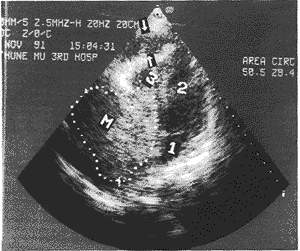

1、左房;2、左室;3、右室;M:为血栓肿块,箭头所指为心包腔低回声结 核肉芽组织,脏壁层心包增厚凹凸不平

图1 缩窄性心包炎伴右房血栓

中国超声医学杂志990744 患者41岁,女性。4个月来无任何原因活动后心悸、气短,并逐渐加重,近2个月平地步 行甚至安静时也感气短,并出现上半身浮肿,腹部胀满,但无晕厥。经一般治疗无效,经超 声心动图发现右心房占位病变而入院。既往无结核病史,检体:体温37.2℃、脉搏68次/分 、血压11.8/9.3Kpa,颜面浮肿,无紫绀。颈静脉怒张,坐位时不消失。肺呼吸音粗糙无罗 音。心界增大、心律整,心音减弱但未闻异常心音及杂音。肝脏肿大至右肋下7cm,有触痛 ,腹部移动性浊音阳性。双下肢凹陷性水肿。化验:血、尿常规及出凝血时间无异常。血沉 第一小时50mm,第二小时120mm。心电图:窦性心动过缓、肢体导联低电压,TV3、V5倒置 。胸部X线:心影扩大、心包未见钙化影,两肺无异常。2DE及CDFI检查:左心系统未见异常 ;右心房增大,可见一巨大非均匀性实质性肿物,几乎占据整个右心房,大小为9.9cm×9 .4cm,大部分回声强度高于室壁,有宽基底与右房后壁紧密相连,无活动性,并延伸至三 尖瓣口(图1)。三尖瓣活动受限。心包不规则增厚,回声增强,心包腔增宽呈不均匀低回声 , 部分脏层心包回声不连续,但无钙化。CDFI右心房内血流纤细,沿肿块心腔侧间隙进入右室 ,上腔静脉扩张血流受阻。肝脏肿大,肝静脉扩张,腹水阳性。超声诊断:右心房占位病变 ,性质待定,缩窄性心包炎,少量心包积液。